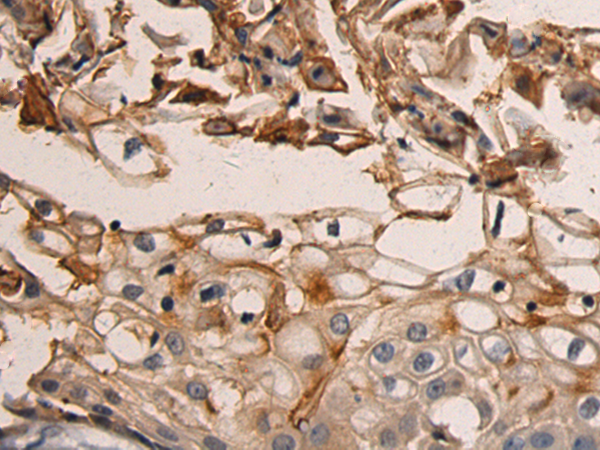

分类: 科研抗体货号: P07783别名: ADCK4; NPHS9应用: IHC反应种属: Human, Mouse, Rat